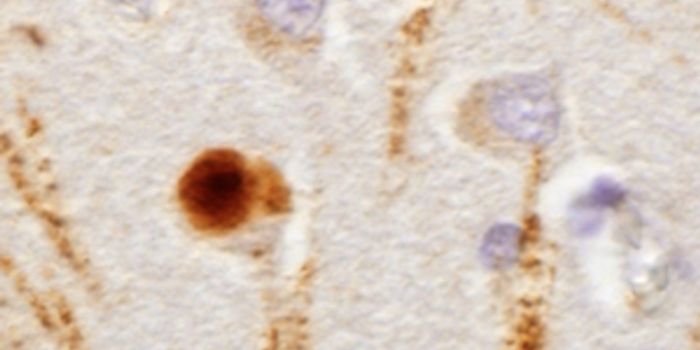

SEP 26, 2018NeuroscienceSolanezumab: this simple name evokes at the same time one of the greatest hopes and the worst disillusions for Alzheimer ...